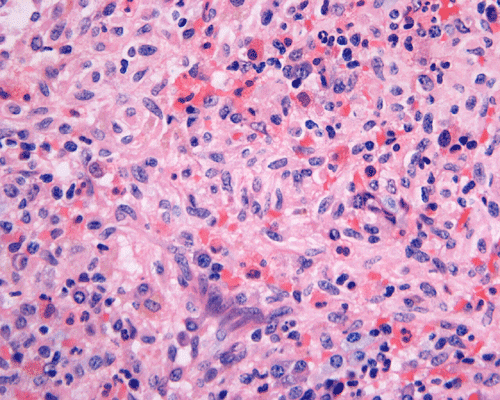

Clinical information: The patient was a 73 year-old man with an itchy skin rash, hepatosplenomegaly, and gastrointestinal bleeding. On admission, his complete blood count (CBC) showed an elevated white count (21,000/cm3) with 25% monocytes and 16% eosinophils, hemoglobin of 9.8 g/dL and 8,000 platelets/cm3. His 24-hour urine histamine was >200 mg/mL (ref 5.6-13.5 mg/mL). A bone marrow biopsy was performed and the representative photomicrographs are illustrated below:

| DIAGNOSIS: Aggressive systemic mastocytosis (WHO classification). |

The patient in the presented case was diagnosed with aggressive systemic mastocytosis, with documented bone marrow, liver and spleen involvement, and succumbed to his disease about two months after the presented biopsy.

Normal mast cells have a round or oval, centrally located nucleus with uniform distribution of dark purple granules in the cytoplasm. Mast cells are well demonstrated by toludine blue and Giemsa stains, and also by immunohistochemistry for CD 117 or tryptase. Napthol ASD chloracetate esterase also highlight mast cells specifically. Mast cells are also positive for CD45, CD33, and CD68 but these markers are less specific than tryptase. Bone marrow aspirations stained with Giemsa are most useful for recognizing atypia in mast cells. It should, however, note that Giemsa stain may be false negative in formalin fided tissue. Hallmarks of atypia in mast cells include spindling of mast cells, hypogranulation, uneven granule distribution, and nuclear lobulation. Recognition of the so-called mast cell granuloma, in which mast cell aggregrates are associated with lymphocytes and eosinophils can be helpful.

In the bone marrow, three morphologic patterns of mast cell accumulation have been recognized. Type I shows focal clusters of mast cells with preservation of bone marrow fat and other hematopoetic elements. The burden of mast cells is more in Type II and usually shows patchy clusters of mast cell replacing bone marrow in a hypercellular marrow background with osteosclerosis and fibrosis. Type III is diffuse replacement of the marrow space with mast cells, often with circulating mast cells in peripheral blood. It is also important to note that mast cells are easily over looked on routine H and E stain or are mistaken for histiocytes.